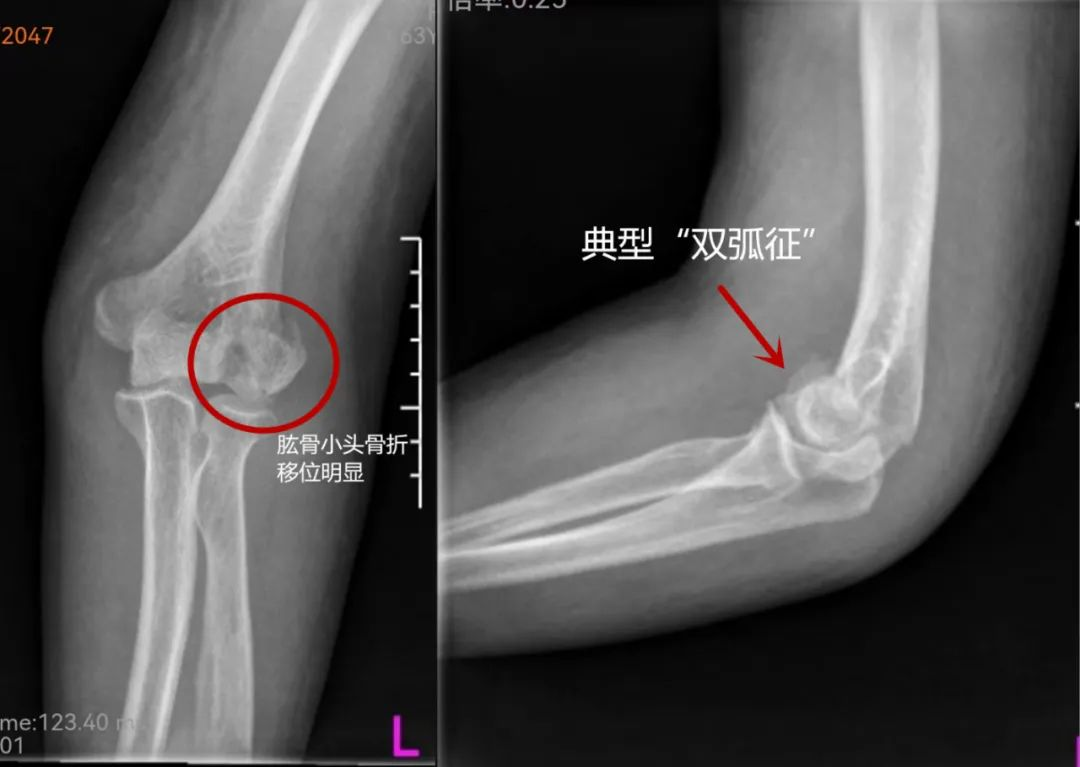

诊断

此外,X线上软骨不显影,实际骨折块要大于X线片显示。所以当可能是此类骨折时,应进行CT平扫加三维重建检查。